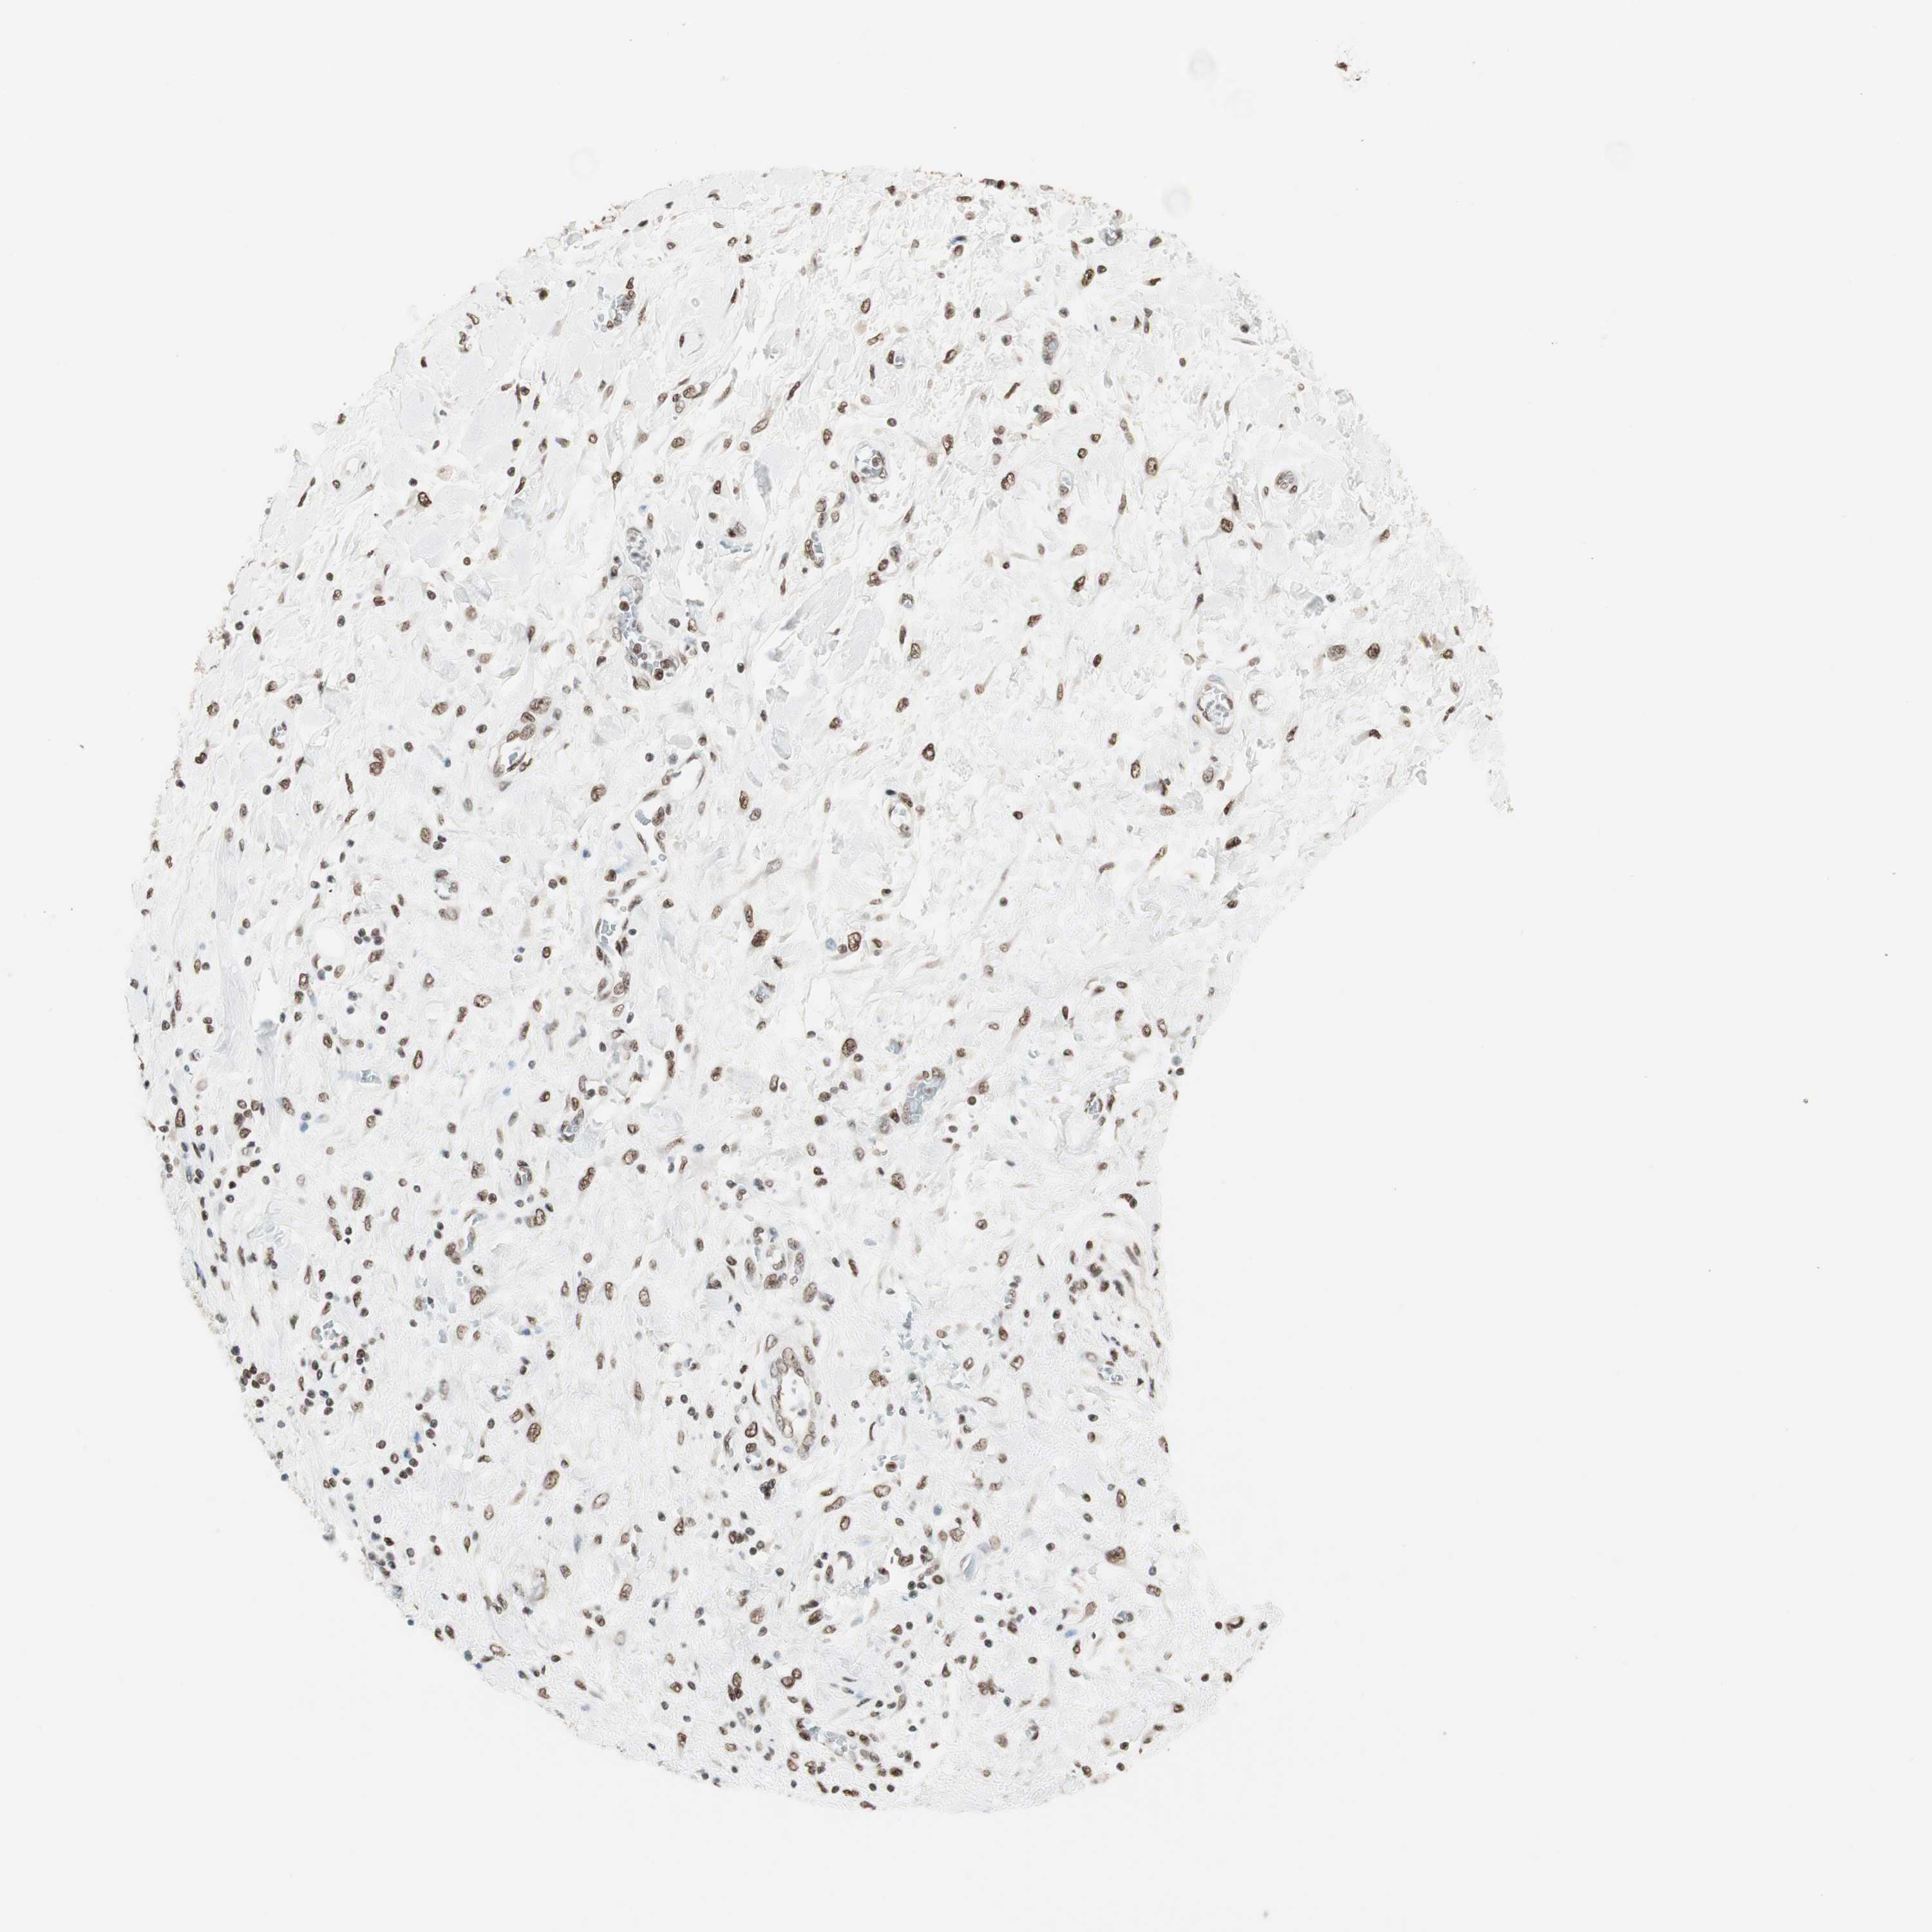

PANCREATIC CANCER - Protein expressioni

A mouse-over function shows sample information and annotation data. Click on an image to view it in a full screen mode. Samples can be filtered based on level of antibody staining by selecting one or several of the following categories: high, medium, low and not detected. The assay and annotation is described here.

Note that samples used for immunohistochemistry by the Human Protein Atlas do not correspond to samples in the TCGA dataset.

Antibody stainingi

Antibody staining in the annotated cell types in the current human tissue is reported as not detected, low, medium, or high, based on conventional immunohistochemistry profiling in selected tissues. This score is based on the combination of the staining intensity and fraction of stained cells.

Each image is clickable and will lead to virtual microscopy that enables deeper exploration of all samples and also displays staining intensity scores, fraction scores and subcellular localization as well as patient and tissue information for each sample.

Antibody HPA003916

Antibody CAB037318

Staining

High

Medium

Low

Not detected

Intensity

Strong

Moderate

Weak

Negative

Quantity

>75%

75%-25%

<25%

None

Location

Nuclear

Cytoplasmic/membranous

Cytoplasmic/membranous,nuclear

Adenocarcinoma, NOS

Adenocarcinoma, metastatic, NOS